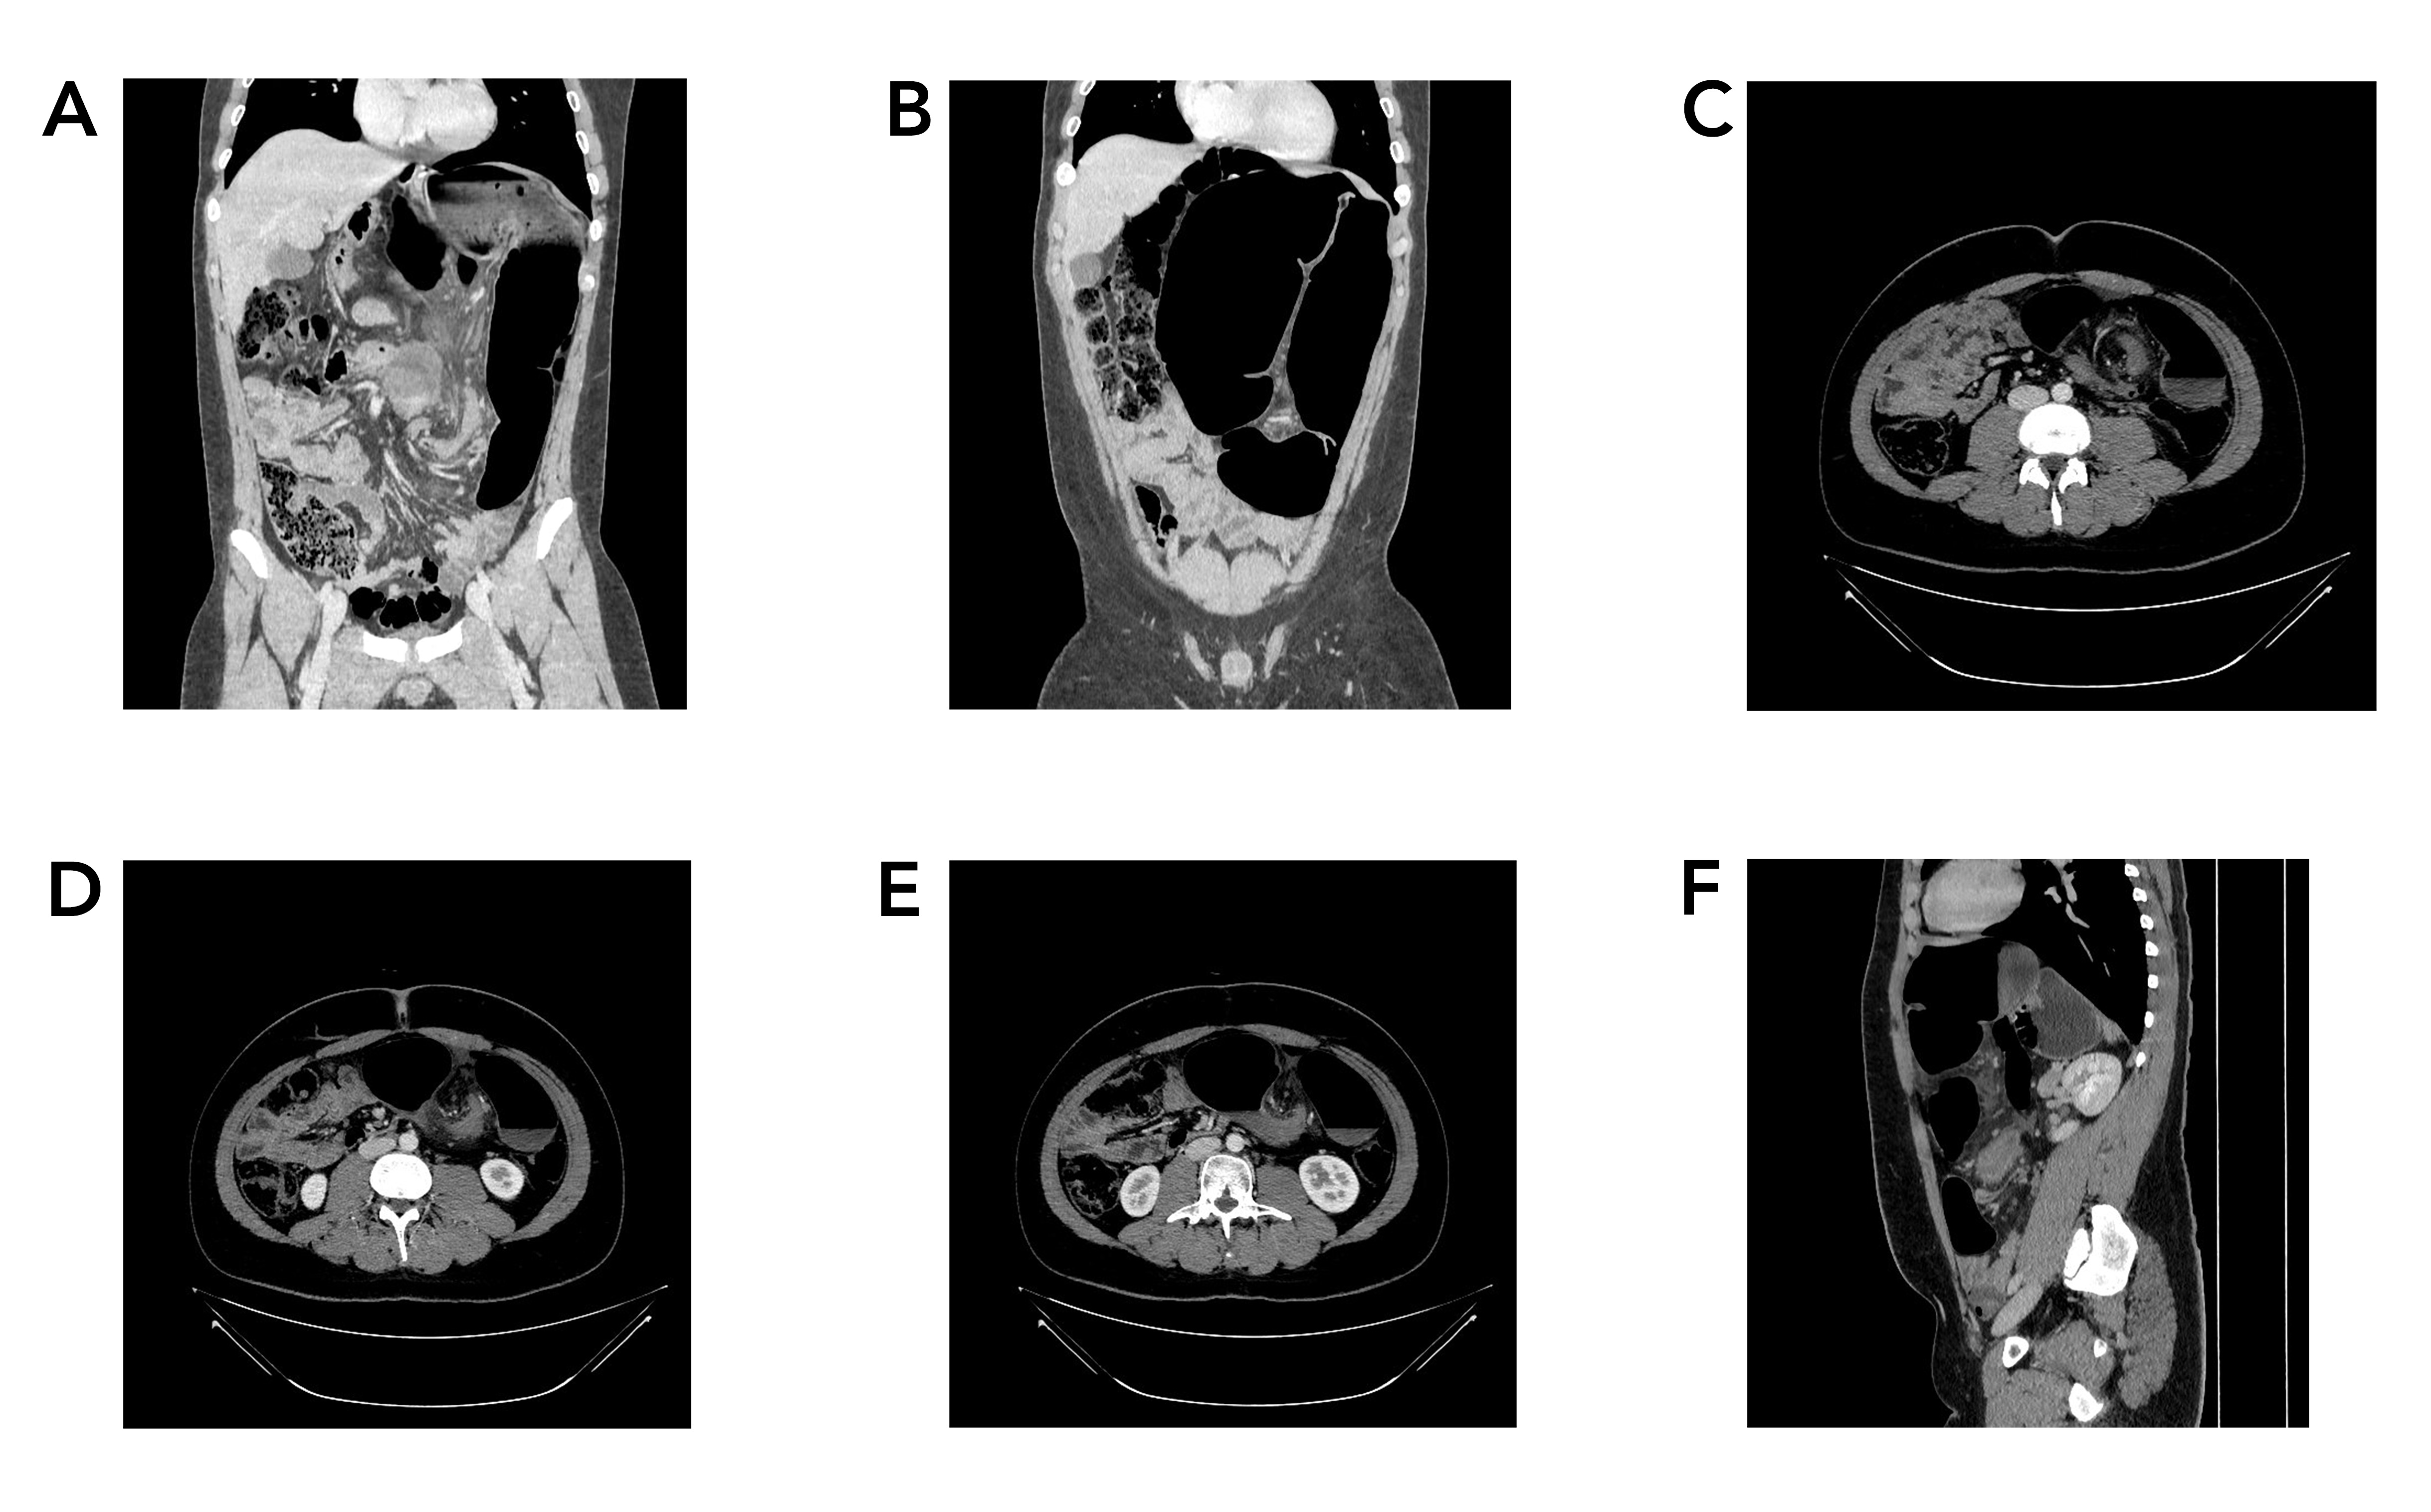

Before thyroxine therapy, in the once-weekly regimen group, the median value of TSH was 9.2 μIU/mL (IQR 6.8 μIU/mL), in the twice-weekly regimen group the level was 9.1 μIU/mL (IQR 7.3 μIU/mL), and in the standard daily dose group the median level was 15.4 (IQR 23.1 μIU/mL). After thyroxine intake and upon follow-up after six months, the TSH level decreased to 4.0 μIU/mL (IQR 3.7 μIU/mL), 4.2 μIU/mL (IQR 5.1 μIU/mL) and 4.5 μIU/mL (IQR 4.9 μIU/mL) in the standard daily, once- and twice-weekly regimen group, respectively (Figure 1) (Table 3). The outcome was statistically insignificant between groups. After six months of follow-up, 56.9% of patients in the daily regimen group, 43.0% in the once-weekly group, and 44.5% in the twice-weekly group achieved TSH levels within the normal reference range (Figure 2).

Compared to the daily treatment group, patients in the once-weekly group had an odds ratio (OR) of 0.659 (95% CI: 0.310–1.398, p = 0.277), and those in the twice-weekly group had an OR of 0.763 (95% CI: 0.363–1.602, p = 0.474), indicating no statistically significant difference in achieving normal TSH between the treatment regimens. Gender was not a significant predictor; males had an OR of 1.845 (95% CI: 0.439–7.751, p =0.403) compared to females. Age and baseline TSH similarly did not significantly influence the likelihood of achieving normal TSH (OR = 0.997, p = 0.801 and OR = 0.995, p = 0.317, respectively) (Table 4).